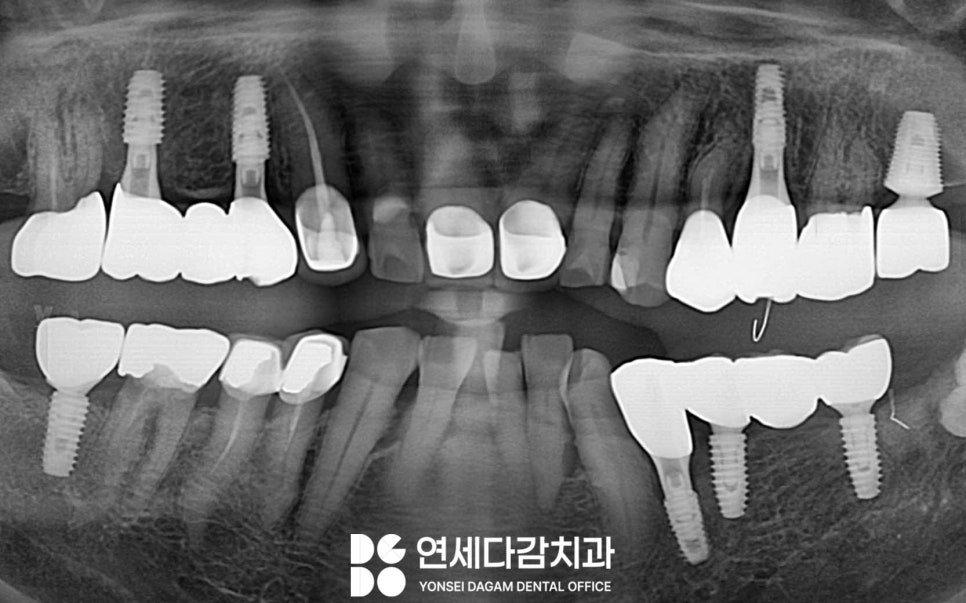

임플란트로 치료했다고 해서

관리를 소홀히 해도 되는 것은 아닙니다.

모든 치료는 본인의 관리 능력에 따라

유지 기간이 천차만별이 될 수 있습니다.

임플란트는 자연치처럼

충치가 생기지는 않아도,

보철 주변으로 치주 질환이

생길 수 있다는 점을 간과해서는 안 됩니다.

가락시장역 치과 에서 강조하는 것은

모든 보철은 자연치처럼

꼼꼼한 관리가 필요하다는 점입니다.

인공 치아라고 해서 관리가

필요 없는 것이 아니라

오히려 더 세심한 주의가 필요합니다.